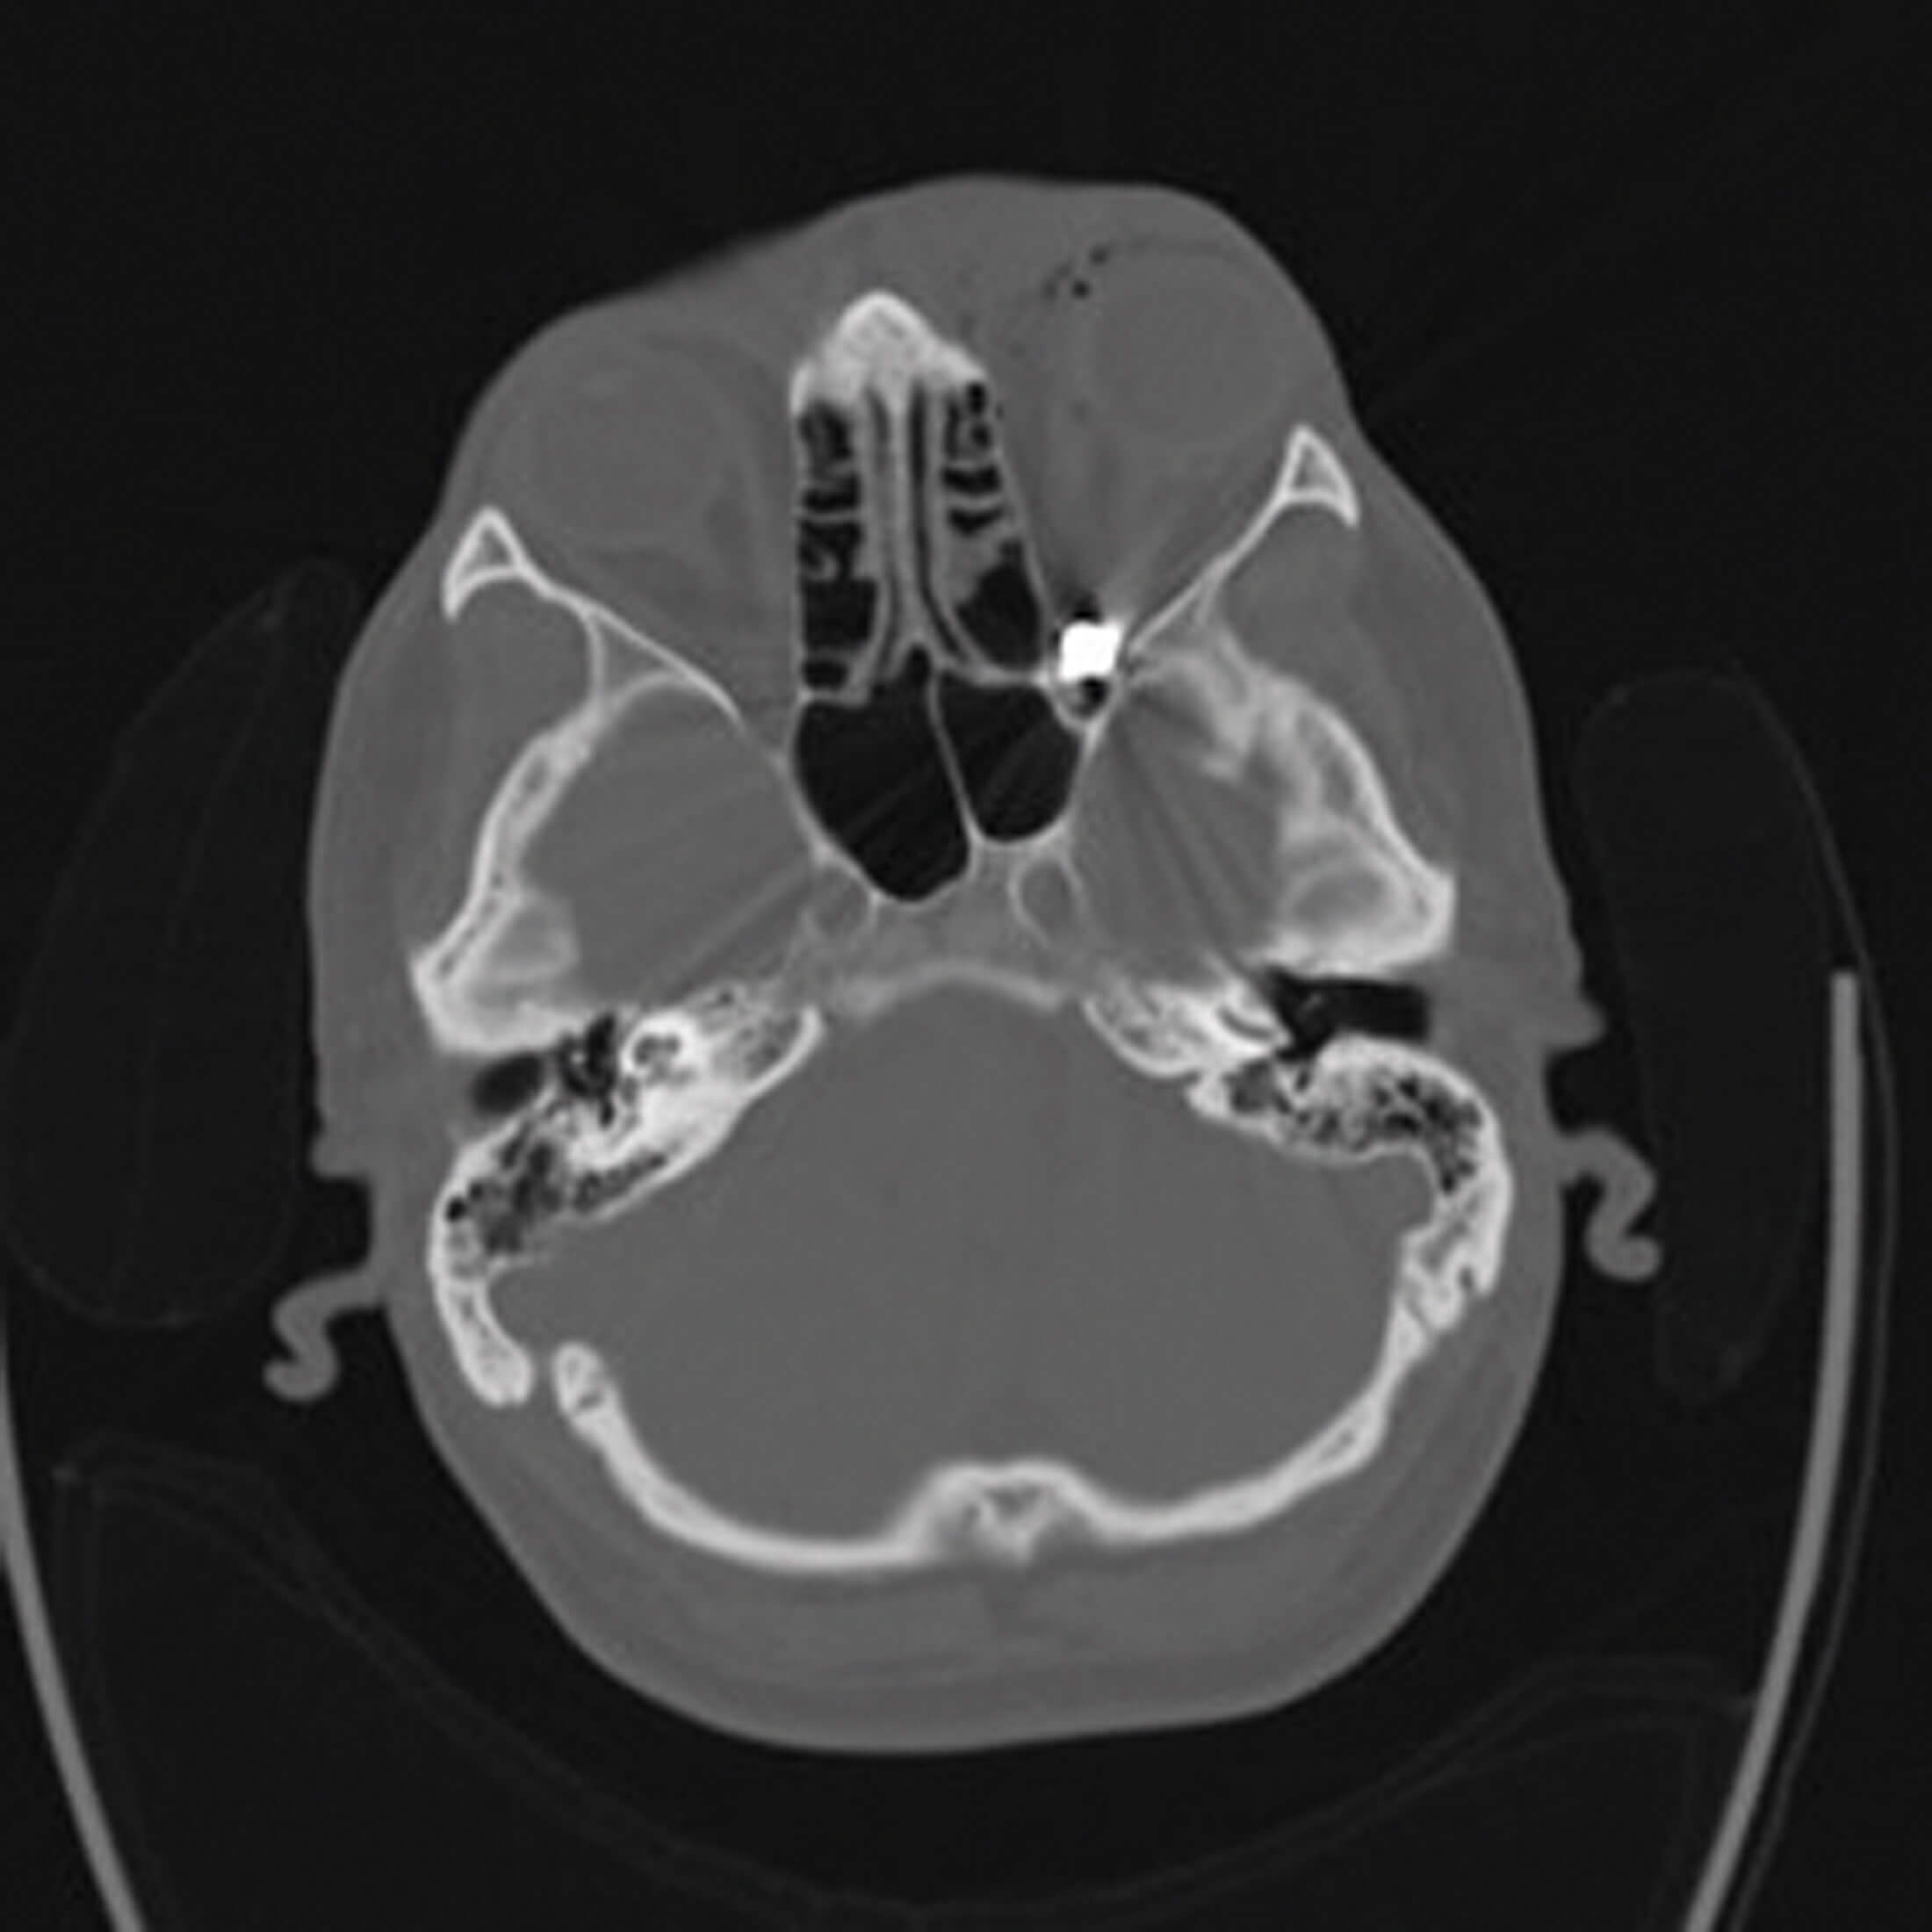

Figure 1: Computed tomography scans of the head showing the presence

of a foreign body with metal effect in the right posterior orbital fossa.

A 30-year-old male presented with left periorbital bruising and a 5mm entry wound over the supraorbital ridge. Initial visual acuity was 6/9 in the right eye and 6/60 in the left eye with a left relative afferent pupillary defect (RAPD) and restricted gaze. Ocular examination revealed vitreous haemorrhage and subretinal haemorrhage. Computed tomography (CT) showed a metallic FB in the left orbital apex causing optic nerve compression (Figure 1). There was proptosis of the left eye. An immediate left lateral canthotomy was performed. Postoperatively, visual acuity in the left eye improved to 6/18 with full extra ocular movement. A review at 20 days postoperatively revealed no pain, no RAPD and left eye acuity of 6/12. Unfortunately, the patient was subsequently lost to follow-up and was uncontactable.